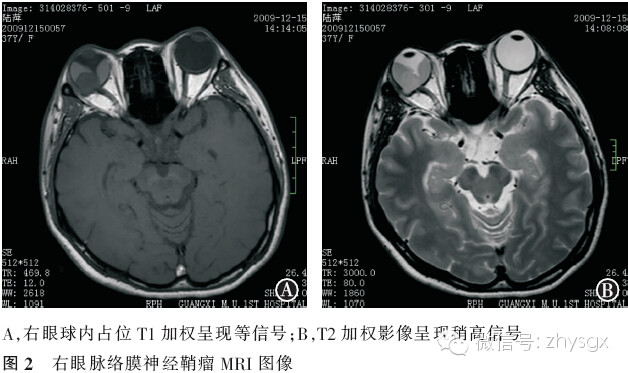

患者,女,37岁,因“右眼视物不清伴眼前黑影遮挡6年,胀痛2年”于2009年12月入院。既往:双眼高度近视,10年前行双眼LASIK手术。眼科检查,视力:右眼无光感,眼压51.7 mmHg;左眼0.8,眼压11.3 mmHg。右眼结膜混合性充血,角膜雾状混浊,前房中深,瞳孔4 mm,对光反射迟钝,晶状体前囊下见棉絮状混浊,眼底窥视不清;左眼检查大致正常。辅助检查:眼部B超示:右眼玻璃体腔内可探及球形实性病变,边界清晰,病变内回声不均匀,并可探及带状回声与其相连,考虑为右眼球内占位,继发性视网膜脱离(见图1);右眼眼轴长27.0 mm,左眼眼轴长26.9 mm。MRI检查示右眼球内后极部可见大小约1.5 cm×1.4 cm的信号灶,病灶信号均匀,边界清晰;相对玻璃体其在T1WI上呈稍高信号,T2WI上呈低信号;相对脑组织其在T1WI上呈等信号,T2WI上呈稍高信号;病灶局部的眼球壁向后突出、隆起;可见视网膜脱离。左眼球及脑部未见明显异常(见图2)。入院诊断:右眼球内肿物,右眼继发性视网膜脱离,右眼继发性青光眼。入院后予降眼压等对症处理,并于2009年12月22日局麻下行“右眼球摘除术”,术中见眼球壁完整,切开后呈鱼肉状。术后病理报告示:脉络膜神经鞘瘤。病理切片HE染色:显微镜观察可见肿瘤细胞为梭形,细胞核细长,深染,呈不典型栅栏状排列,部分呈束状排列。免疫组织化学染色:肿瘤细胞分别对S-100染色呈阳性,波形蛋白(Vimentin)染色呈阳性,胶质纤维酸性蛋白(glial fibrillary acidic protein,GFAP)、增殖细胞核抗原(Ki-67)、平滑肌肌动蛋白(smooth muscle actin,SMA)染色均呈阴性(见图3)。

眼内神经鞘瘤的临床表现无特异性,易误诊为黑色素瘤。有文献指出MRI可能能帮助我们鉴别葡萄膜神经鞘瘤与黑色素瘤[4-5]。黑色素瘤的MRI特点为:在T1加权影像呈现高信号,T2加权影像呈现低信号。葡萄膜神经鞘瘤则不同,相对脑组织而言,神经鞘瘤在T1加权影像呈现等信号,T2加权影像呈现等信号或高信号。因此,MRI表现为位于葡萄膜的孤立性、边界清楚的占位性病变,其相对脑组织T1加权影像呈现等信号,又伴随视网膜脱离时,临床医生要注意神经鞘瘤的可能。